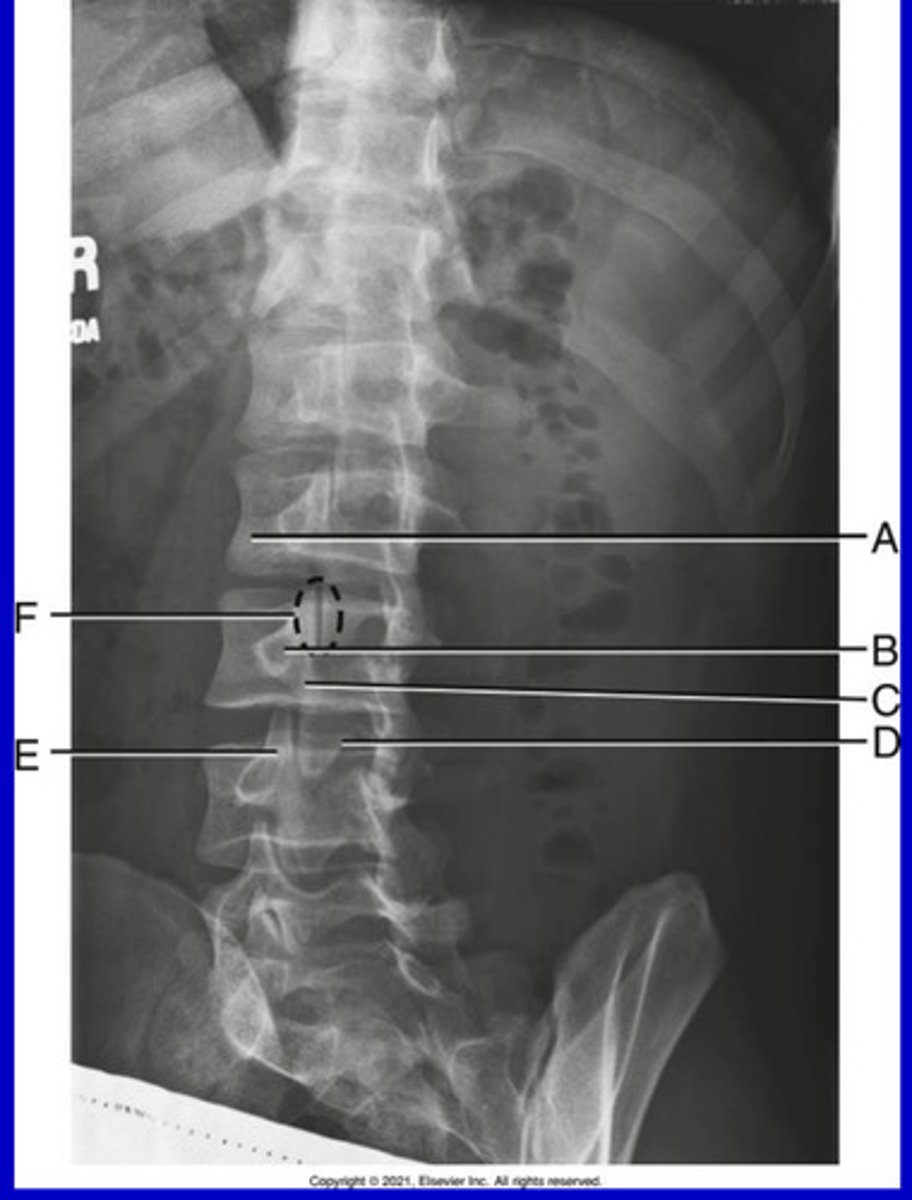

L2 Pedicle

A.

L2-3 intervertebral foramina

B.

L3-4 intervertebral joint space

C.

L4 body

D.

L5-S1 articular process

E.

Sacrum

F.

Greater sciatic notch

G.

L5-S1 joint

H.

Lateral Lumbar

What position?